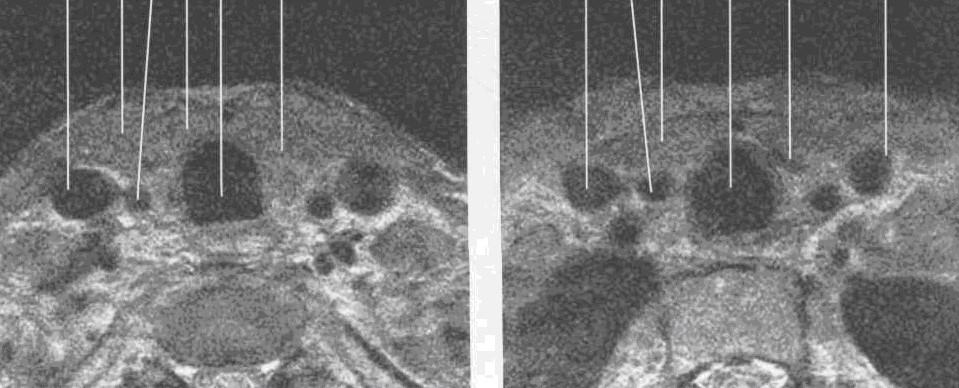

Рис. 28. Серия КТ изображений щитовидной железы на разных уровнях щитовидного хряща в аксиальной плоскости.